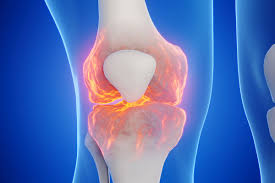

관절염

관절염은 무릎 구부릴 때 통증의 가장 흔한 원인 중 하나입니다. 나이가 들면서 무릎 관절의 연골이 마모되고, 이는 통증과 염증을 유발합니다. 관절염은 퇴행성 변화로 인해 발생하는 경우가 많으며, 일반적으로 노인에게서 더 많이 나타납니다. 관절염으로 인한 통증은 구부릴 때 더욱 심하게 느껴질 수 있으며, 이는 일상적인 활동에 큰 지장을 줄 수 있습니다.

- 반월판 손상: 무릎 내의 반달 모양의 연골이 손상되면 심한 통증이 발생할 수 있습니다.